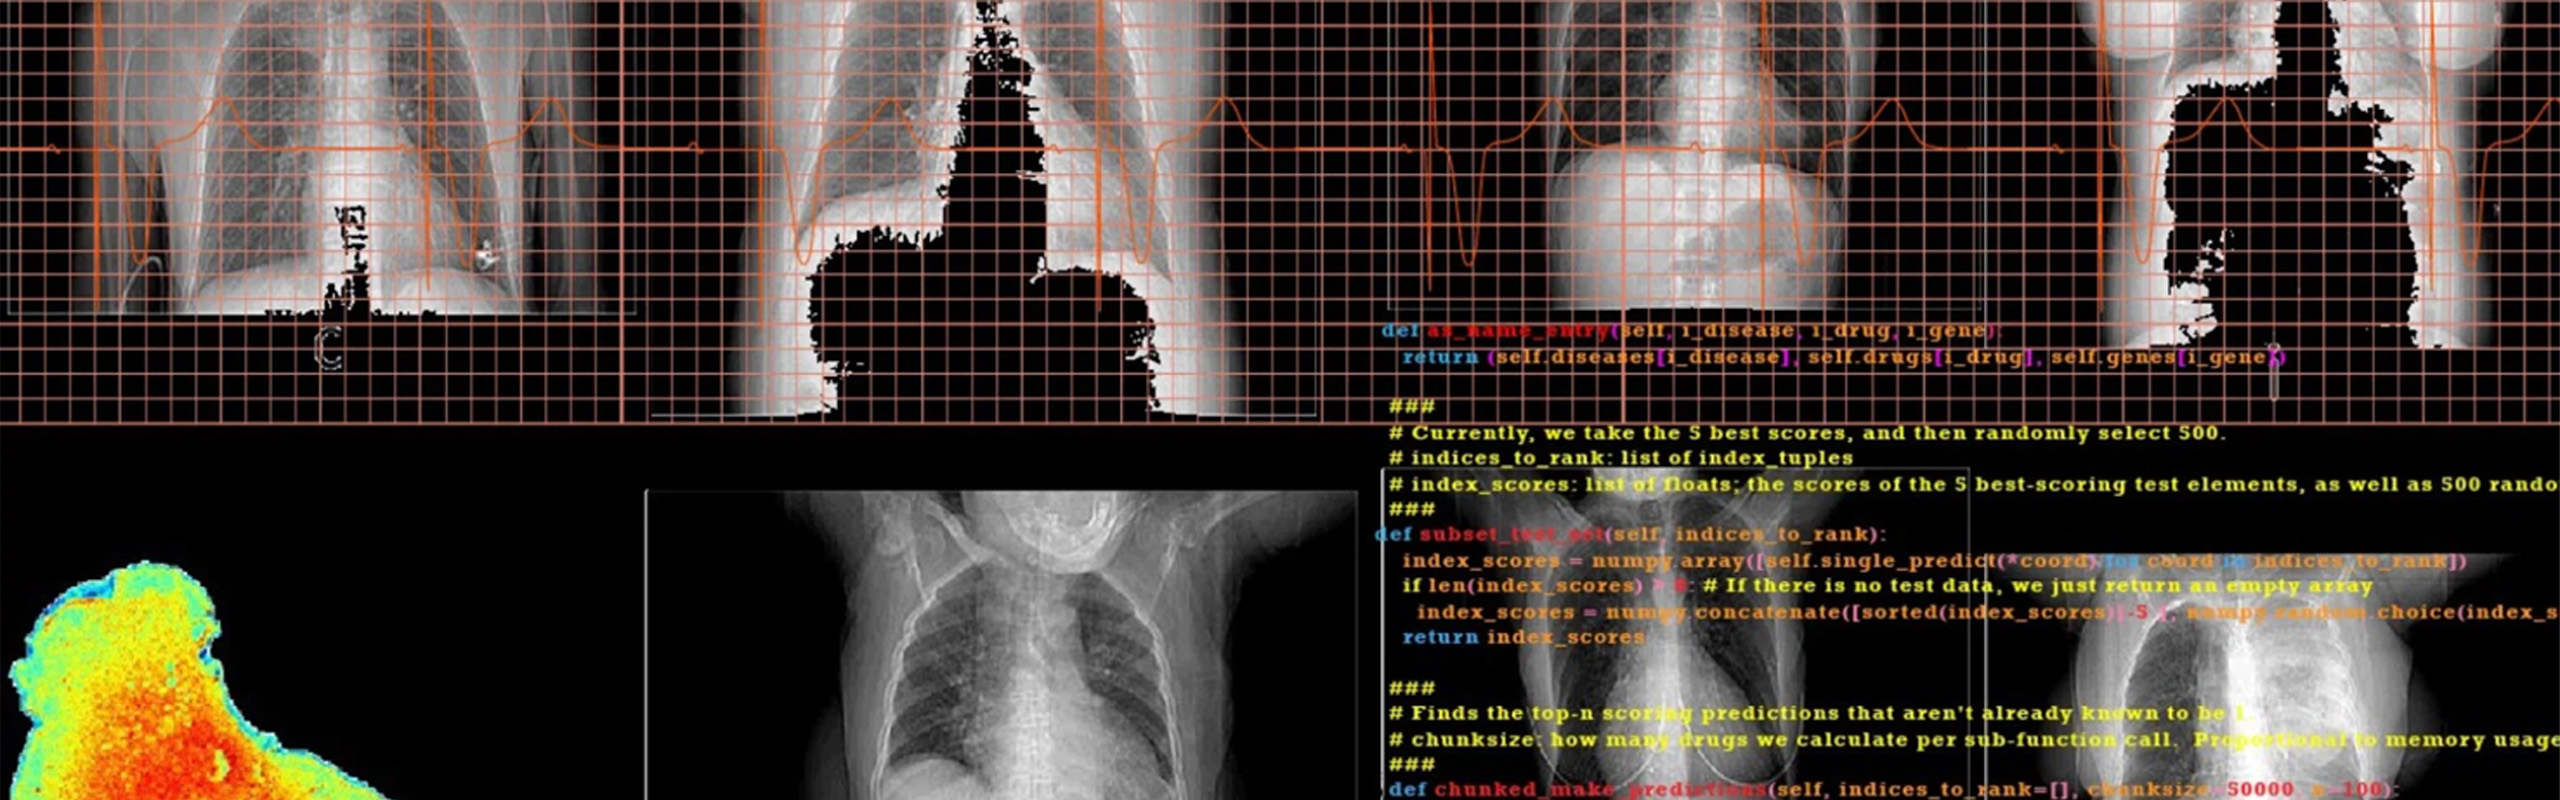

The U-HackMed initiative was first launched in 2018 as a biomedical hackathon by the Lyda Hill Department of Bioinformatics. The program aimed to bring together bioinformaticians and clinicians for solving complex biomedical data problems using computational biology, which was a huge success and led to another biomedical hackathon event in 2019. Due to the COVID-19 pandemic, the program was re-configured as a virtual Gap Year for 2020 when students from across the nation formed teams and worked together on specific biomedical big data analysis problems. After a hiatus in 2021, we launched the U-HackMed NeuroChats global Journal Club. This initiative was jointly sponsored by the Peter O’Donnell Jr. Brain Institute and the Lyda Hill Department of Bioinformatics at UT Southwestern. All computational resources and support for our U-HackMed projects is provided by our on-site infrastructure BioHPC team. Read more about our sponsors, resources, and programs below.